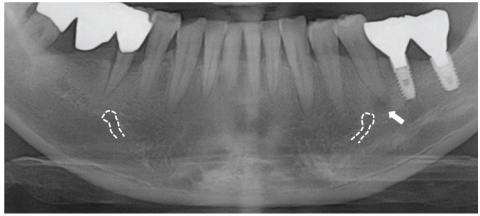

Figure 4

Location of mental foramens (dotted line) and periapical radiolucency (arrow).

Figure 4 Location of mental foramens (dotted line) and periapical radiolucency (arrow).